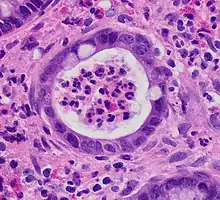

Histologic

Biopsies of the mucosa are taken during endoscopy to confirm the diagnosis of UC and differentiate it from Crohn's disease, which is managed differently clinically. Histologic findings in ulcerative colitis includes: distortion of crypt architecture, crypt abscesses, and inflammatory cells in the mucosa (lymphocytes, plasma cells, and granulocytes).[28] Unlike the transmural inflammation seen in Crohn's disease, the inflammation of ulcerative colitis is limited to the mucosa.[28]